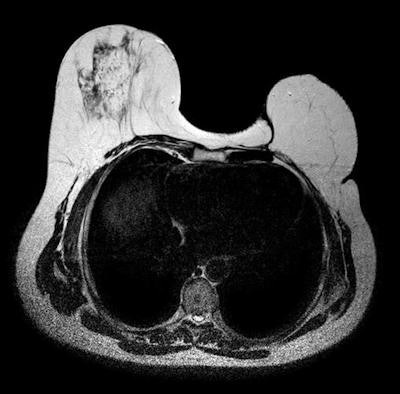

Because of its high spatial resolution and contrast between implants and soft tissues and lack of ionizing radiation, MR is the most useful imaging modality for characterizing breast implants. It has the highest sensitivity and specificity for implant rupture, due to its sequences that can suppress or emphasize the signal from silicone. Also, it can differentiate intracapsular from extracapsular rupture and assess the extent of silicone leakage into the breast parenchyma and granuloma formation, noted Dr. Sergi Juanpere, from the department of radiology-IDI at Dr. Josep Trueta University Hospital in Girona, Spain.

MRI can reliably reveal collapsed intracapsular rupture by detecting shell fragments floating inside the silicone gel implant ("linguine sign"). This sign is often associated with extracapsular rupture. An uncollapsed silicone implant rupture may be seen as a subtle silicone invagination between the inner shell and fibrous capsule, known as the "teardrop sign" or the "keyhole sign." Other imaging signs, such as the "salad oil sign" or "droplet sign," are nonspecific and not reliable without other MRI evidence of implant rupture, but these signs should prompt a search for subtle signs of intracapsular rupture, according to Juanpere.

MRI's sensitivity for rupture is between 80% and 90%, and its specificity is between 90% and 97%. It may be used to exclude a ruptured prosthesis, and can show the presence and extent of silicone leakage better than other imaging techniques. Despite this, conventional breast imaging techniques are the methods of choice when breast implant failure is suspected because well-defined and discernible sonographic features have been established for ruptured implants. Moreover, MRI is more expensive, and many women have contraindications -- cardiac pacemakers, aneurysm clips, metallic foreign bodies, and claustrophobia -- to MRI, he wrote.